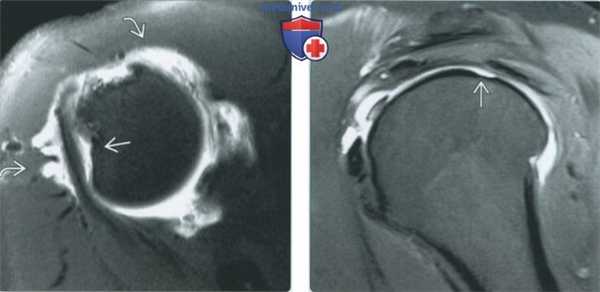

(Справа) МР-артрография в режиме PD FS, сагиттальный срез, этот же пациент: отмечается смещение кпереди связочно-хрящевого комплекса. Также выявляются компоненты смещенных шовных фиксаторов. Средняя суставно-плечевая связка не изменена. (Слева) МР-артрография в режиме Т1 ВИ, коронарный срез, этот же пациент: визуализируется смещение восстановленного участка суставной губы. Контрастный препарат распространяется за пределы сустава. Прилежащий отдел суставного хряща почти полностью отслоился. Каналы от шовных фиксаторов выглядят как гипоинтенсив-ныелинии.

(Справа) МР-артрография в режиме Т2 ВИ FS, коронарный срез, этот же пациент: отмечается распространение контрастного препарата через дефект в восстановленном участке. Выявляется дефект верхней суставной губы, который в режиме Т1ВИ не определялся из-за отсутствия заполнения контрастным препаратом. (Слева) Рентгенография, передне-задняя проекция: определяются обширные послеоперационные эрозивные изменения головки плечевой кости и суставной впадины лопатки, свидетельствующие о хондролизе. Такие изменения могут быть обусловлены термической или химической травмой.